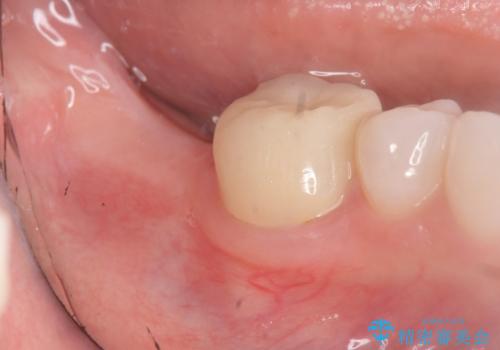

![[ インプラント体・カスタムアバットメント・ジルコニアクラウン ] インプラントの構造の症例 治療前](https://seimitsushinbi.jp/wp/wp-content/uploads/2024/02/d7b3d7509c0cc77833268d7096e1730b-500x350.jpg?v=1708928260)

![[ インプラント体・カスタムアバットメント・ジルコニアクラウン ] インプラントの構造の症例 治療後](https://seimitsushinbi.jp/wp/wp-content/uploads/2024/02/4f5d249988cfa0d7689dd16755d46820-500x350.jpg?v=1708928265)